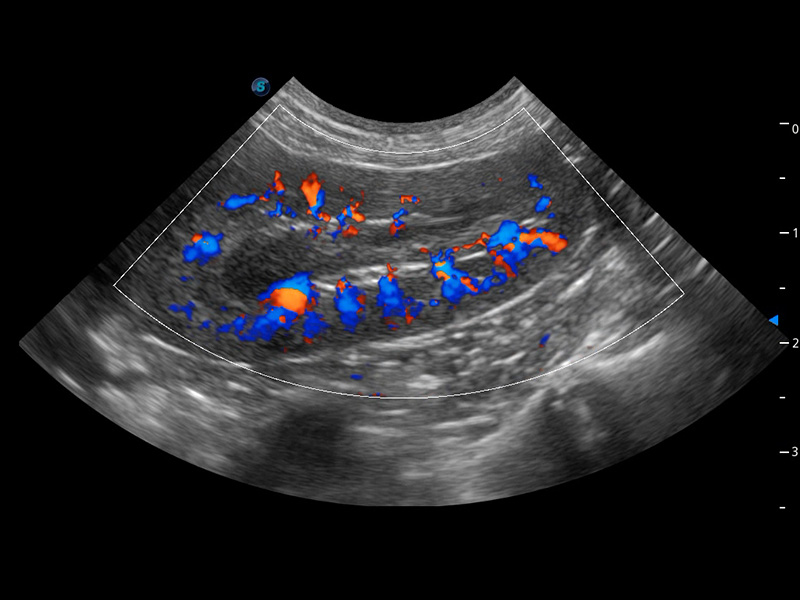

(犬)四腔心血流